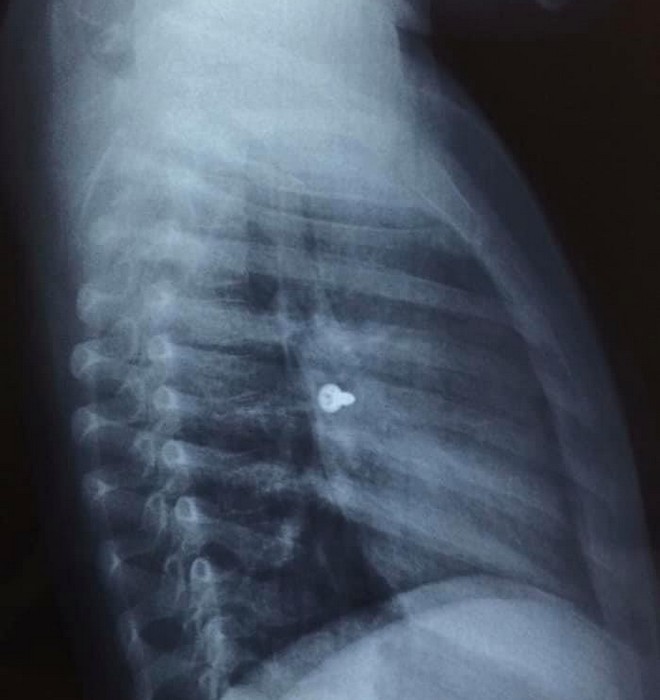

Εικόνα από την ακτινογραφία facebook Emmanuel Prokopakis

Απίστευτες μοιάζουν οι εικόνες από τις ακτινογραφίες ενός 3χρονου κοριτσιού από την Κρήτη που κατάπιε βίδα, η οποία κατέληξε στον αριστερό του πνεύμονα.

Αμέσως έγιναν οι απαραίτητες ακτινογραφίες που έδειξαν πως η βίδα βρισκόταν στον αριστερό πνεύμονα του παιδιού.